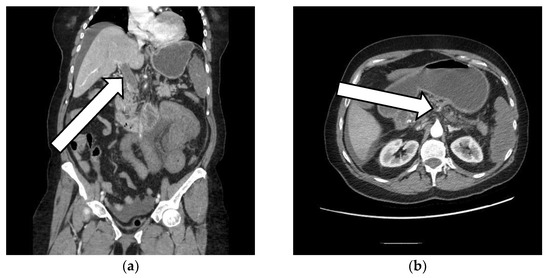

Portal Vein and Mesenteric Artery Thrombosis Following the Administration of an Ad26.COV2-S Vaccine—First Case from Romania: A Case Report

2. The Case Presentation